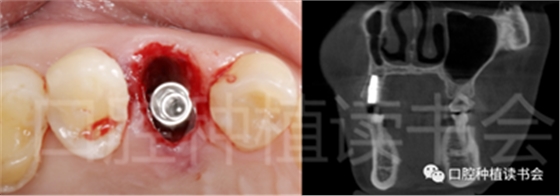

5.3.3 根據(jù)拔牙窩內(nèi)的牙槽間隔高度,植入康盛CANSUN柱形親水種植體(4.3*8mm),確保種植體肩臺與牙槽間隔平齊,種植體的所有表面均被自體骨包繞(圖16),植入扭矩為25N.cm。

圖16 盡量讓種植體表面被牙槽間隔的自體骨包繞。

5.3.6 術后即刻CBCT(美亞光電)檢查種植體軸向及深度良好(圖19)。

圖19 術后即刻CBCT確認種植體頰、

舌側(cè)骨板完整,并保持了足夠的厚度。